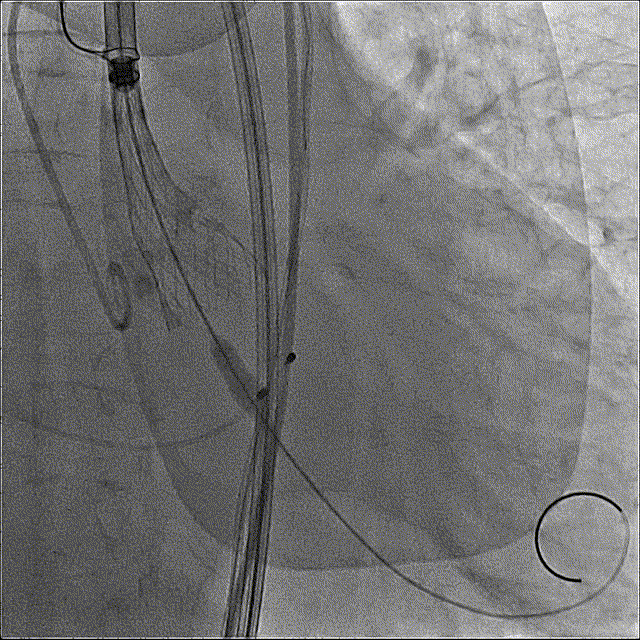

瓣膜开花造影

瓣膜工作位造影